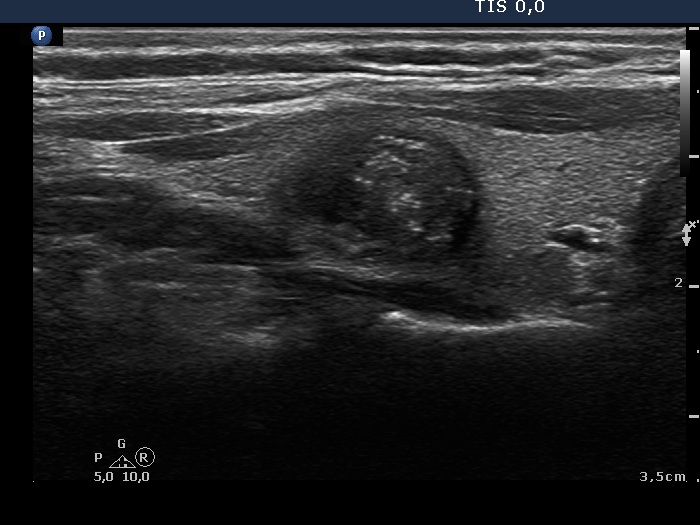

Papillary carcinoma (histological diagnosis) - case 469 |

![]() |

This tumor contained numerous punctate echogenic foci (microcalcifications). |